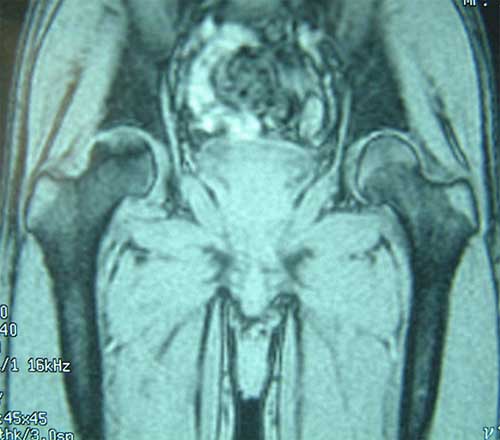

股骨头缺血性坏死MRI显示坏死区                  微创手术方法,采用隧道减压刮除死

BMP植入,异体骨支撑,恢复形态       手术后24个月X线片,关节塌陷未加重,关节功能良好,无疼痛